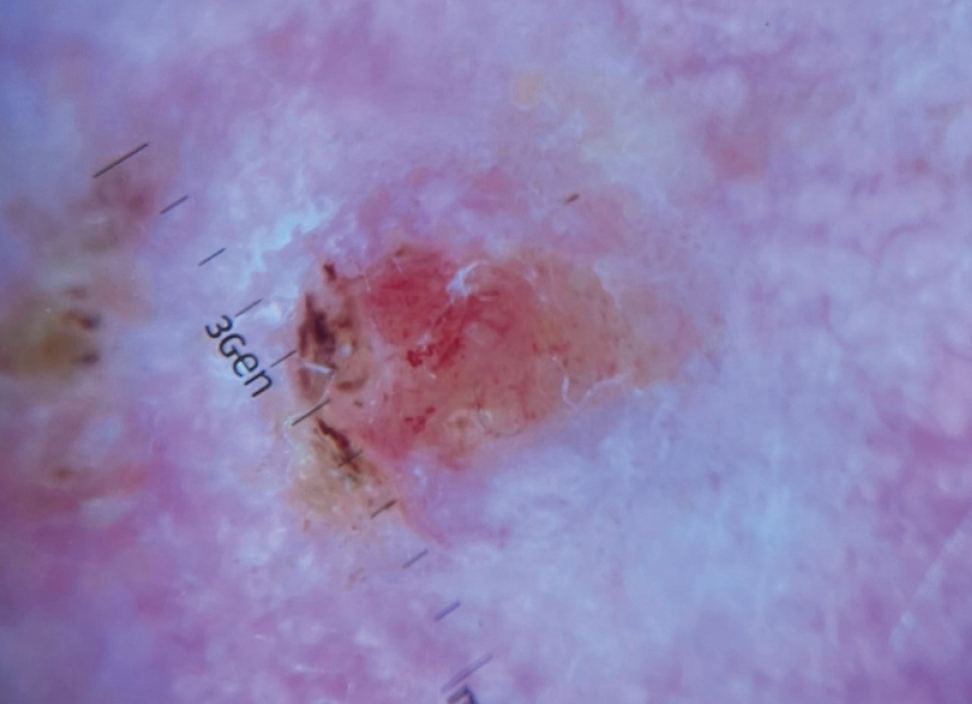

При осмотре (status localis) на коже головы определяется узел розовой окраски, плотной консистенции диаметром около 1 см (рис. 1). Дерматоскопически выявлены атипичные линейные и точечные сосуды, структуры по типу хризалид, корочки (рис. 2). Процесс протекает на фоне множественных рубцов после криодеструкции, очагов актинического кератоза, также выявлен и гистологически верифицирован очаг плоскоклеточной карциномы (рис. 3, 4).

Рис. 2. Дерматоскопическая картина атипичной фиброксантомы: атипичные сосуды, хризалиды, корки.

Fig. 2. Dermatoscopic picture of atypical fibroxanthoma: atypical vessels, chrysalides, crusts.